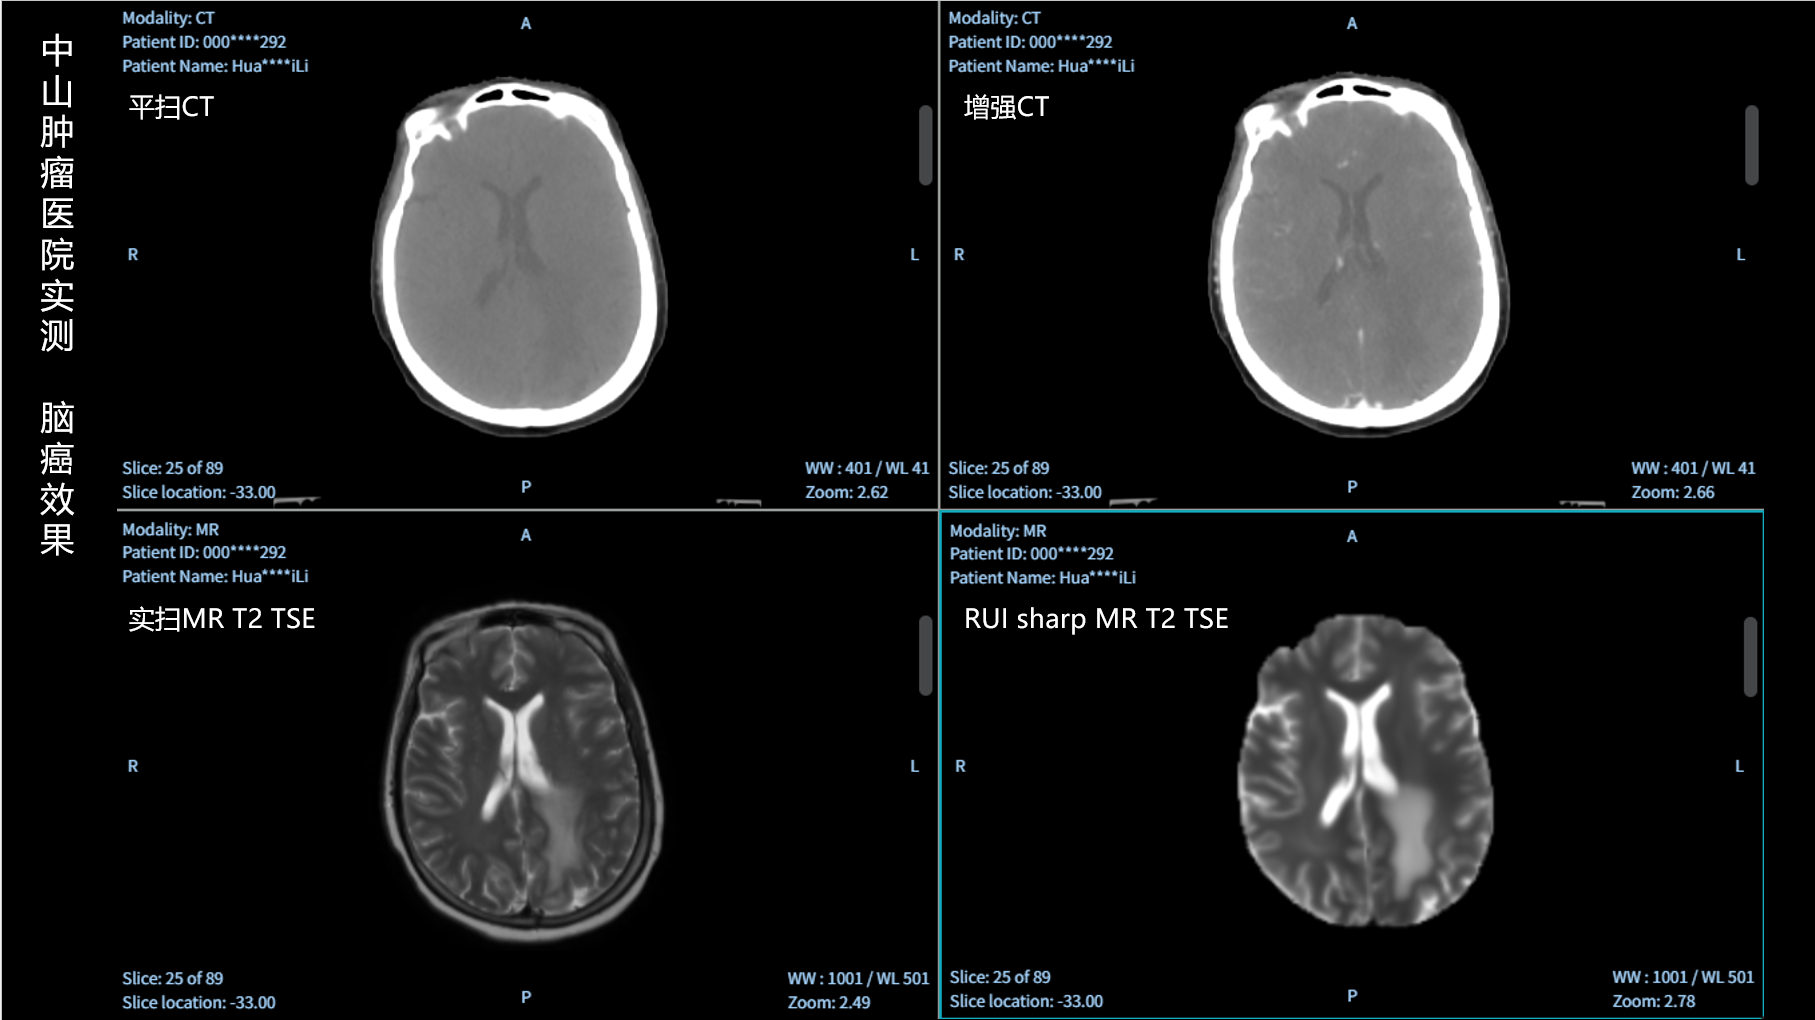

RUI sharp H(锐影)可在不依赖MRI的前提下,显著提升头部CT图像的软组织分辨率,为临床提供更高质量的辅助信息,尤其适用于MRI资源受限或较难配准的头颈部放疗感兴趣区勾画场景。

可大幅提高头部CT影像软组织分辨率,使肿瘤和周边器官显示更清晰,为放疗靶区勾画提供参考。

无需图像配准,CT和锐影图像同源,可匹配、叠加、"淡入淡出"显示。

实测效果